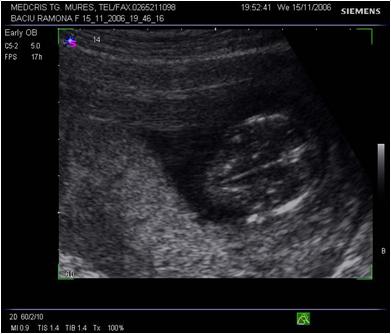

Fig. nr.112 Sarcina 12 saptamani la ecografia transvaginala